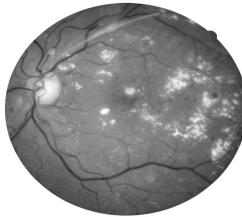

Observe a retinografia abaixo.

Fonte: Arquivo da Banca Elaboradora.

Nesse caso, é correto afirmar que